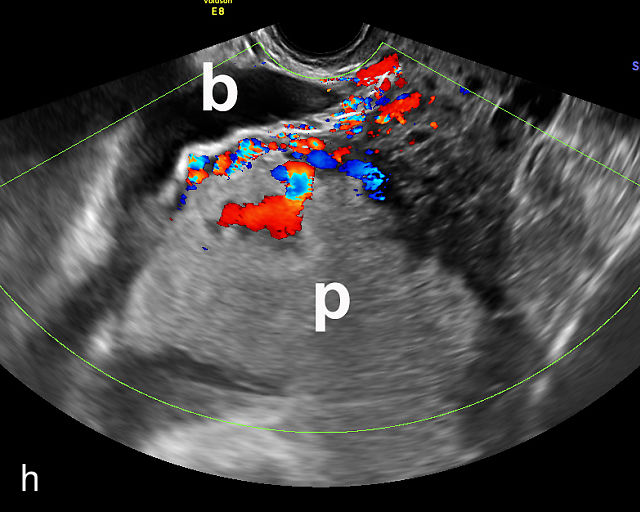

Placenta previa and low-lying placenta. (a) Transabdominal grayscale ultrasound image suspicious for placenta previa. The placenta (PL) appears to overlie the internal cervical os (CX). Note the time stamp: 2:19:37. (b) Transvaginal ultrasound of the same patient taken approximately 50 minutes later. Note the time stamp: 3:10:25. The internal os and the lower placental edge are both clearly seen, and the placenta does not overlie the internal os. Because the lower placental edge is 1.93 cm from the internal os, it will likely resolve by the third trimester. (c) Transabdominal grayscale ultrasound of placenta previa. The placenta (p) covers the cervix, but the cervix, especially the internal os, cannot be visualized due to shadowing. (d) Transabdominal grayscale ultrasound of placenta previa. The placenta (p) covers the cervix (c) but shadowing obscures adequate visualization. The internal os is indicated by the arrow. (e) False-positive image of placenta previa on transabdominal grayscale ultrasound. The bladder (b) is full, pushing the anterior and posterior walls of the lower uterine segment (ls) together making it appear that the placenta (p) overlies the internal os of the cervix. In reality, the line depicted by the arrowheads is where the anterior and posterior walls of the lower segment are in proximity to each other. The cervix is much lower and is obscured by shadowing (c). (f) Transabdominal grayscale ultrasound image of placenta previa. The placenta (p) covers the cervix (c), but the cervix, especially the internal os, cannot be visualized due to shadowing. b, bladder. (g) Transvaginal grayscale ultrasound image of placenta previa. The placenta (p) completely covers the internal os (arrow) of the cervix (c). The internal os can be seen clearly. h, fetal head. (h) Transvaginal grayscale ultrasound image of posterior low-lying placenta (p). The lower placental edge is clearly seen and is 1.56 cm from the internal os (arrow) of the cervix (c). The placental edge and the internal os are clearly seen. h, fetal head. (i) Transvaginal grayscale ultrasound image of a posterior placenta previa (p). The internal cervical os is clearly seen (arrow). c, cervix. (j) Transvaginal grayscale ultrasound image of an anterior placenta previa (p). The internal cervical os is clearly seen (arrow). c, cervix; h, fetal head. (k) Transvaginal grayscale ultrasound image of a posterior placenta that was thought to be low-lying on transabdominal sonography but could not be adequately assessed. This examination clearly shows the lower edge of the placenta (p) to be 2.18 cm from the internal os (arrow) of the cervix, firmly establishing that the placenta is not low-lying and allowing the patient to undergo labor safely and deliver vaginally. c, cervix. (l) Transvaginal grayscale ultrasound image of placenta previa. The placenta (p) completely covers the internal os (arrow) of the cervix (c). The internal os can be seen clearly.

Most cases of placenta previa will be suspected prenatally by transabdominal ultrasound.49 However, this approach has several limitations and may be inaccurate.72,73,74 because the relationship between the placenta and the internal cervical os may be difficult to assess by transabdominal ultrasound.72,73,74 The bladder may be full, pushing the anterior and posterior walls of the lower uterine segment together, falsely creating the impression of a placenta previa (Figure 5e).61 There may be considerable shadowing, including by the fetal presenting part, which may limit the accuracy of transabdominal ultrasound (Figure 5d,f).75 Posterior placentas may be more difficult to assess.

Transvaginal ultrasound overcomes these limitations (Figure 5g–l).72,73,74,76 The probe is inserted into the vagina and therefore is closer to the region of interest.51,61 In addition, transvaginal transducers have higher frequencies and superior resolution compared to transabdominal transducers. Transvaginal ultrasound is safe and is not associated with increased bleeding.72,73,74,75,76 As such, transvaginal ultrasound should be the imaging modality of choice whenever there is suspicion of placenta previa.49,67,77